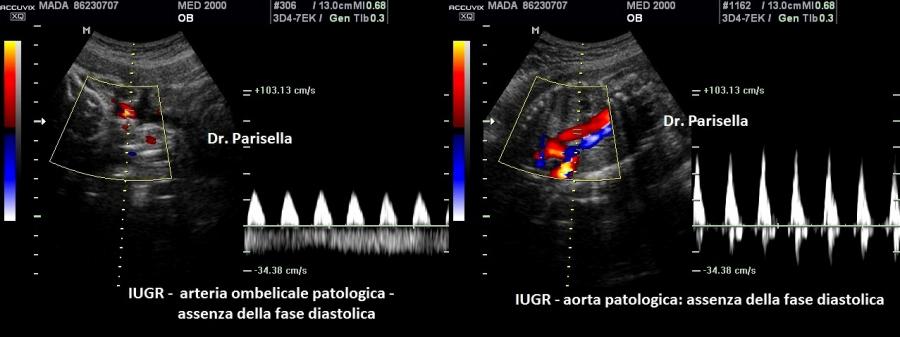

4) IUGR;